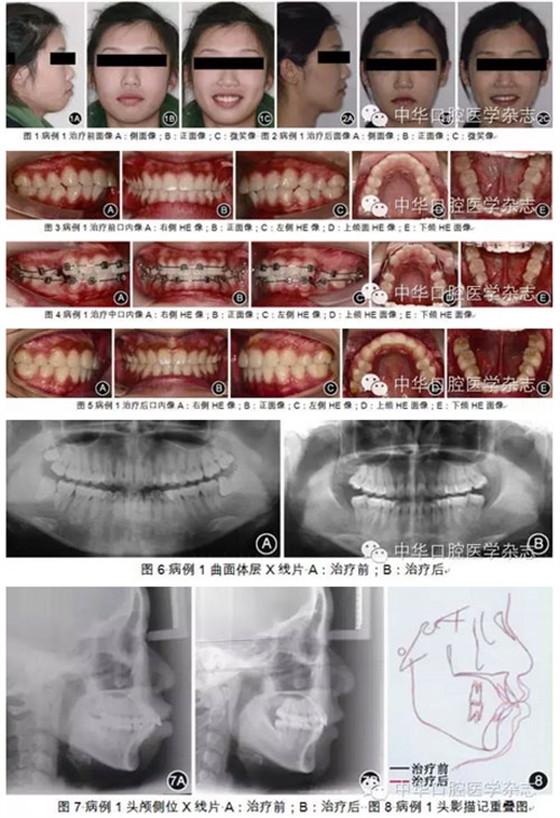

理解骨骼類型:正畸診斷和治療必須與生長發(fā)育協(xié)調(diào);對于異常的生長型,須采取必要的措施進(jìn)行調(diào)整或補(bǔ)償。因此,個(gè)性化診斷時(shí)需從以下5個(gè)方面進(jìn)行綜合分析,即面部美觀、骨骼類型、牙量與骨量不調(diào)、矢狀向關(guān)系不調(diào)和生長發(fā)育。首先需對患者正側(cè)貌進(jìn)行整體評估,對面形理想的患者,治療時(shí)應(yīng)維持。側(cè)貌受3方面因素影響:①牙齒位置,上切牙位置直接影響唇的位置:上下唇均由上切牙支撐,且上下切牙位置密切相關(guān),牙齒位置直接影響唇的突度,進(jìn)而影響面形。②骨骼結(jié)構(gòu),正畸醫(yī)師應(yīng)意識到骨骼結(jié)構(gòu)的異常也是面部失衡的重要因素,一定程度的骨骼結(jié)構(gòu)異??赏ㄟ^改變牙齒位置代償。對于下頜平面角(FMA)為高角的患者,可通過更多地直立下切牙代償骨骼異常,改善面形。而對于下頜平面角為低角的患者,下切牙則可維持在原來相對唇傾的位置。因此,下頜平面角、后面高(PFH)、前面高(AFH)及PFH/AFH等骨骼結(jié)構(gòu)垂直向測量項(xiàng)目在個(gè)性化診斷系統(tǒng)中十分重要。③軟組織厚度,在和諧的面形中,唇厚度與頦厚度常一致;若頦厚度不足,則需進(jìn)一步直立下切牙代償。充分分析牙齒位置、骨骼結(jié)構(gòu)以及軟組織情況,可幫助正畸醫(yī)師獲得更多的關(guān)于面部美觀的信息,有助于判斷是否可通過牙齒代償改善面形。分析側(cè)貌形態(tài)時(shí)通過Z線(側(cè)貌線)可客觀判斷面部突度。Z線為連接頦部和唇部最突點(diǎn)的連線,其與眶耳平面所形成的后下角為Z角。正常的Z角為70°~80°,理想值為75°~78°。作為FMIA角的外在表現(xiàn),Z角在評價(jià)軟組織側(cè)貌時(shí)敏感性高,是下頜平面角、FMIA角和軟組織厚度3個(gè)指標(biāo)的綜合體現(xiàn)。骨骼結(jié)構(gòu)分析應(yīng)從以下幾方面進(jìn)行:①下頜平面角,下頜平面角是顱頜面骨骼分析中重要的測量項(xiàng)目,其可同時(shí)反映面下1/3的垂直向和矢狀向生長,正常范圍為22°~28°。PFH、AFH及PFH/AFH則是面下1/3垂直高度更直接的測量指標(biāo)。高角患者需要牙齒更大程度的舌向直立代償,治療難度也較大。②SNA角、SNB角、ANB角反映了上下頜骨相對于顱底及其矢狀向位置,而AO-BO距(Wits值)在代表上下頜骨矢狀向相對位置方面,比ANB角更敏感。除面部和骨骼因素外,牙量與骨量不調(diào)也需認(rèn)真考量??谇蝗S空間內(nèi)牙列的大小是有限的,即牙列的前部、后部、側(cè)方和垂直界限。在牙列三維空間的框架內(nèi)分別測量矯治前、中、后段所需的間隙,包括擁擠量及直立切牙改善面形所需的間隙。上下頜牙列矢狀向關(guān)系不調(diào)主要涉及磨牙關(guān)系不調(diào),矯正Ⅱ類或Ⅲ類磨牙關(guān)系均需間隙。測量方法為上頜第一前磨牙頰尖至下頜第一、第二前磨牙鄰接隙間距離。生長發(fā)育也是診斷中需考慮的因素。青少年下頜升支因生長向后改建,從而增加間隙。男性16歲和女性14歲前,每年可增加3 mm的間隙,之后則基本無增加可能。以上顱面形態(tài)分析和全牙列間隙分析共同構(gòu)成了個(gè)性化診斷系統(tǒng)。臨床上,根據(jù)Z角判斷側(cè)貌,決定是否需通過內(nèi)收直立下切牙改變FMIA角來改變患者側(cè)貌,再根據(jù)顱面垂直向(高角或低角)和軟組織形態(tài)決定如何改變患者側(cè)貌:當(dāng)下頜平面角正常時(shí),F(xiàn)MIA角應(yīng)為68°;當(dāng)下頜平面角>28°時(shí),下前牙則應(yīng)更直立代償,F(xiàn)MIA角為65°。頦部軟組織厚度不夠時(shí)下切牙也應(yīng)適度代償直立。FMIA角每增大1°,則需要0.8 mm的間隙。而顱面骨骼矢狀向是否正常(SNA角、SNB角、ANB角、Wits值)決定是否需對治療目標(biāo)進(jìn)行一定程度的妥協(xié),減少下切牙的移動(dòng)量。根據(jù)以上項(xiàng)目結(jié)合全牙列間隙分析、磨牙關(guān)系、患者生長發(fā)育潛力,就能明確治療錯(cuò)HE畸形所需的間隙,從而為臨床醫(yī)師確定減數(shù)方案提供定量參考。經(jīng)典方絲弓矯治技術(shù)個(gè)性化診斷系統(tǒng)還包括治療難度的評估。Gramling通過對安氏Ⅱ類錯(cuò)HE矯治與否進(jìn)行分組對比,分析顱頜面?zhèn)让残螒B(tài)、牙列及牙列關(guān)系對療效的影響,得出各測量項(xiàng)目偏離正常值時(shí)對畸形治療難度的貢獻(xiàn)權(quán)重及難度系數(shù)。測量分析中超出正常范圍的數(shù)值乘上相應(yīng)難度系數(shù)構(gòu)成難度指數(shù)。顱面形態(tài)的難度指數(shù)以及全牙列間隙的難度指數(shù)共同組成總的難度指數(shù),其為治療預(yù)后的評估、治療過程的管理有重要指導(dǎo)意義。圖1~8所示患者為牙型Ⅰ類、骨型Ⅱ類、嚴(yán)重雙頜前突、露齦笑的20歲女性,顱面分析難度指數(shù)為64,顱面及牙列總難度指數(shù)合計(jì)為97.75,說明患者矯治難度中等。牙列間隙分析顯示排齊內(nèi)收前牙需19 mm間隙,而全牙列間隙不足共37.5 mm,根據(jù)經(jīng)典方絲弓個(gè)性化診斷系統(tǒng),提示患者需減數(shù)4顆第一前磨牙和4顆第三磨牙。采用定向力矯治技術(shù)治療后患者面形協(xié)調(diào)。下頜平面角和PFH/AFH得到較好的保持。下切牙從108.5°直立到90°,上切牙得到內(nèi)收并壓低。Z角從50.5°增加至72.5°。因此,經(jīng)典方絲弓定向力矯治技術(shù)中的個(gè)性化診斷系統(tǒng)是內(nèi)容全面、使用方便的診斷分析系統(tǒng),為正畸醫(yī)師提供了清晰的治療路線圖。任何治療技術(shù)都是為了實(shí)現(xiàn)其治療理念所設(shè)計(jì)的。以Tweed醫(yī)師的治療目標(biāo)和治療理念為基礎(chǔ),Merrifield醫(yī)師將原來的12組弓絲簡化為4~5組弓絲,凝練成簡單、高效而原理更完善的定向力矯治技術(shù),其具有以下特點(diǎn)。1.按順序分次粘接矯治器和按順序分次移動(dòng)牙齒對減數(shù)第一前磨牙的病例,第一恒磨牙暫時(shí)不粘接矯治器,錯(cuò)位嚴(yán)重的前牙也可暫時(shí)不結(jié)扎或僅做被動(dòng)結(jié)扎。由此第二前磨牙至第二恒磨牙的托槽間距較長,可使弓絲更有效地作用于第二恒磨牙;患者感覺舒適,也可節(jié)省醫(yī)師的椅旁時(shí)間。隨著第二恒磨牙位置逐漸遠(yuǎn)中直立,分別在1、2個(gè)月后粘接上頜第一恒磨牙、下頜第一恒磨牙托槽。使牙齒在有效的控制下快速而精確地分次定向移動(dòng)。Tweed醫(yī)師嘗試用Ⅲ類牽引對所有下頜后牙進(jìn)行一次性支抗預(yù)備,雖然部分病例取得成功,但常導(dǎo)致下頜前牙唇向傾斜壓低。Merrifield醫(yī)師采用高位J鉤牽引和10顆牙作為支抗,每次移動(dòng)2顆牙,使支抗預(yù)備更可控、有序而精確,稱為Merrifield的“10-2”支抗預(yù)備技術(shù)。在治療初期牙列預(yù)備階段,下頜第二恒磨牙已被直立后傾至合適位置,下牙列分別通過尖牙遠(yuǎn)中移動(dòng)和垂直曲內(nèi)收切牙關(guān)閉拔牙間隙,再依次進(jìn)行下頜第一恒磨牙和第二前磨牙的支抗預(yù)備。3.使用定向力系統(tǒng)控制牙移動(dòng)是經(jīng)典方絲弓矯治技術(shù)的精髓和重要標(biāo)志所謂定向力矯治系統(tǒng),即所有矯治力均應(yīng)引導(dǎo)患者牙列和頜骨產(chǎn)生治療所需反應(yīng),而避免矯治力的不良反應(yīng)。弓絲和牽引力的作用應(yīng)相互協(xié)同,對于未成年患者,矯治力的治療作用應(yīng)與生長發(fā)育協(xié)調(diào);對于成年患者,治療作用則不應(yīng)干擾牙列與其周邊環(huán)境的正常關(guān)系,使下頜平面、HE平面、腭平面與眶耳平面的關(guān)系保持不變或?qū)⒆兓刂朴谶m度范圍內(nèi)。治療時(shí)發(fā)現(xiàn)不良變化應(yīng)及時(shí)調(diào)整矯治力。當(dāng)然,對于Ⅲ類錯(cuò)HE或下頜平面角為低角等需要垂直向擴(kuò)張、下頜平面后下旋轉(zhuǎn)的患者,則可采用不同的矯治力系統(tǒng)。正畸矯治力若不加以控制則可產(chǎn)生不良作用。由于牙齒本身有HE向萌出和近中移動(dòng)趨勢,未加控制的整平可引起磨牙升高;天然牙列下頜磨牙常前傾而有Spee曲度,矯治時(shí)若不預(yù)先直立而直接施加頜內(nèi)矯治力,作為支抗的磨牙則易前傾升高,Ⅱ類牽引的垂直向分力則可加劇下頜磨牙的升高。以上作用均可使下頜向后向下旋轉(zhuǎn),產(chǎn)生頦部后縮、下前牙唇傾、面下1/3變